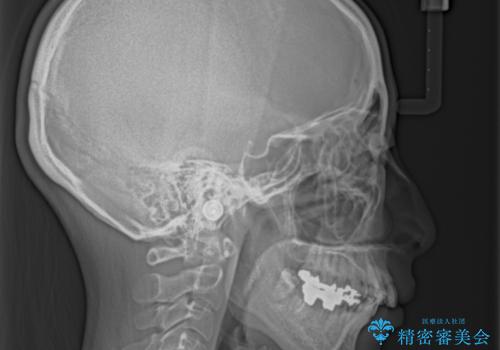

- 上顎前歯が叢生により前方に出ている状態や、全体的なむし歯を気にして来院された患者様です。

口元の突出感を改善するために小臼歯4本を抜歯することとしましたが、左下は大臼歯が欠損していたため、そのスペースを活用し、小臼歯を3本抜歯して治療を行うこととしました。

目立たないハーフリンガル矯正を希望され、裏側装置はどうしても清掃性が低下し、むし歯発生のリスクが高まるため、矯正治療前にしっかりとむし歯治療を行い、矯正治療後にセラミックによる補綴治療を行うこととしました。